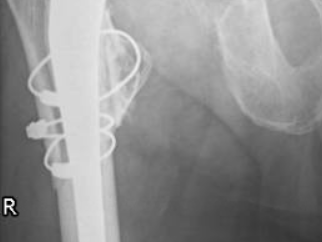

Cas 1. Luxation fémoro-acétabulaire de PTH

Cas 2. Luxation intra-prothétique de PTH